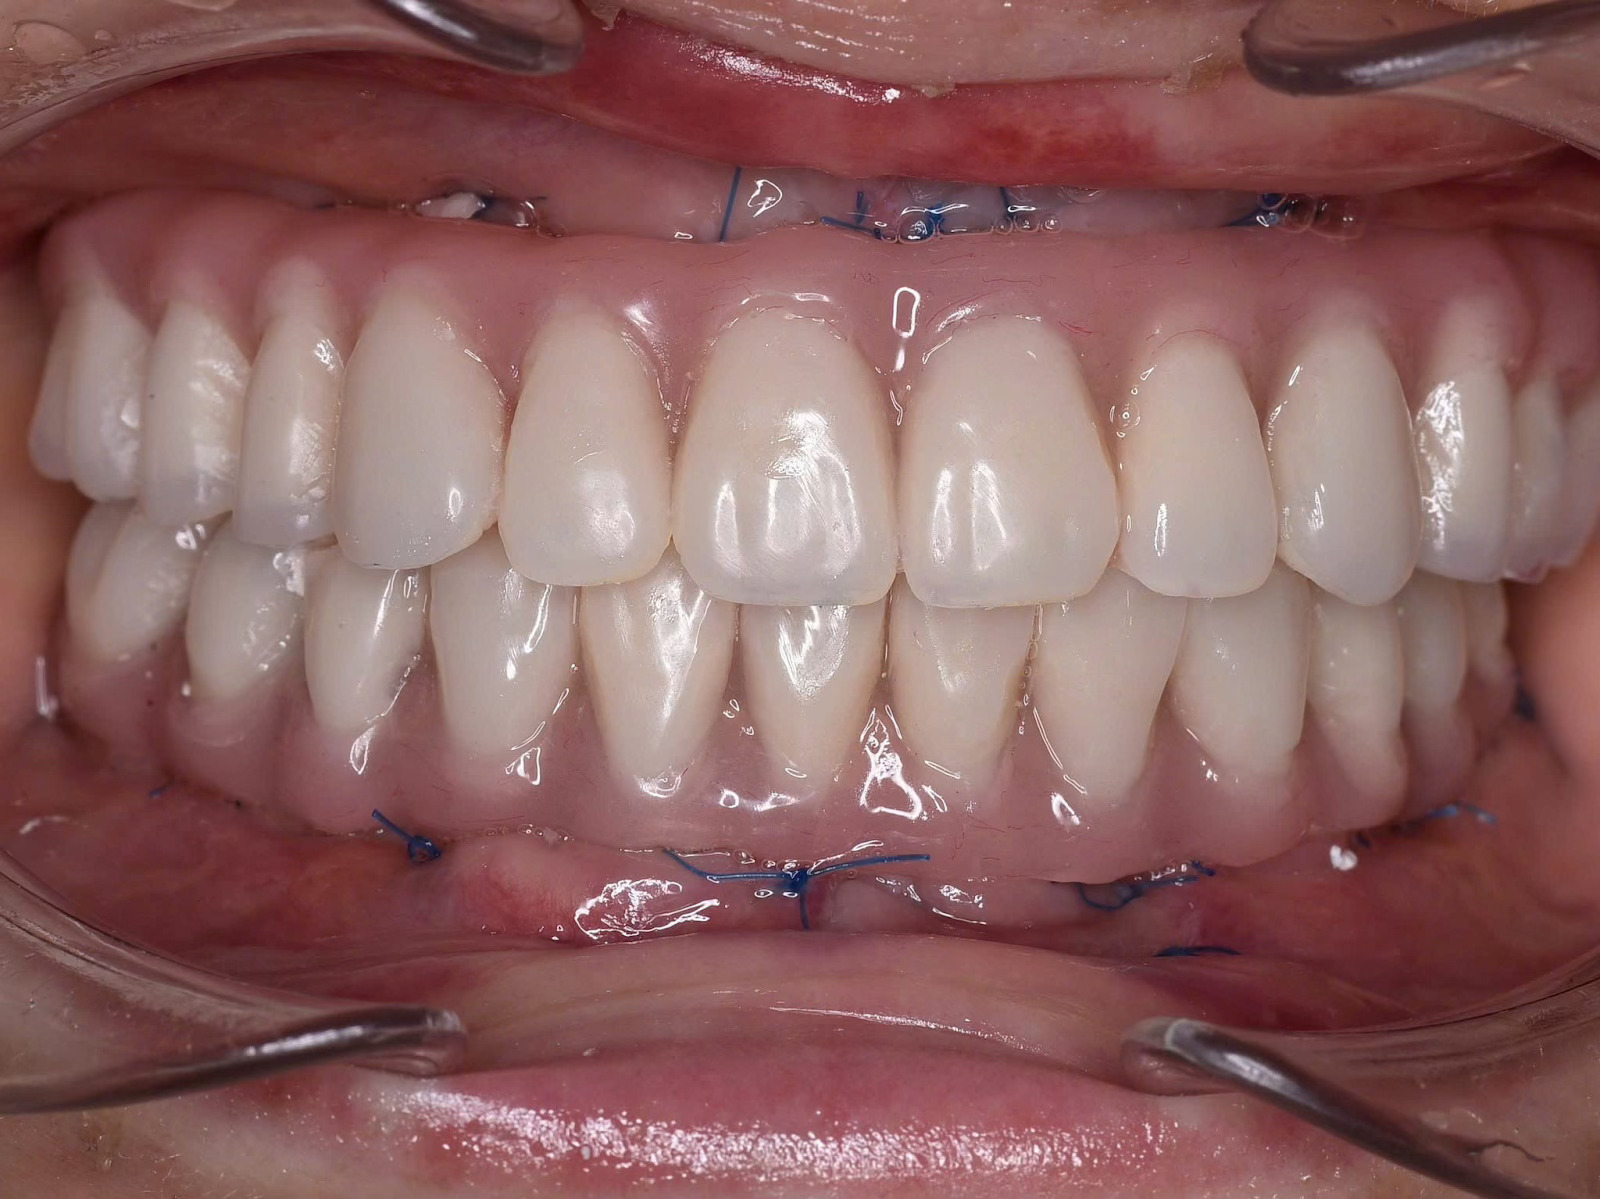

Cấy ghép Implant toàn hàm và phục hình tức thì sau 24h tại Nha Khoa Như Ngọc (21 Trần quang diệu, Hà Nội)